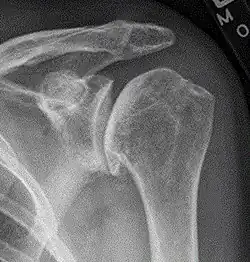

The shoulder joint is composed of three bones: the clavicle (collarbone), the scapula (shoulder blade), and the humerus (upper arm bone) (see diagram). Two joints facilitate shoulder movement. The acromioclavicular (AC) joint is located between the acromion (part of the scapula that forms the highest point of the shoulder) and the clavicle. The glenohumeral joint, to which the term "shoulder joint" commonly refers, is a ball-and-socket joint that allows the arm to rotate in a circular fashion or to hinge out and up away from the body. The "ball" is the top, rounded portion of the upper arm bone or humerus; the "socket," or glenoid, is a dish-shaped part of the outer edge of the scapula into which the ball fits. Arm movement is further facilitated by the ability of the scapula itself to slide along the rib cage. The capsule is a soft tissue envelope that encircles the glenohumeral joint. It is lined by a thin, smooth synovial membrane.